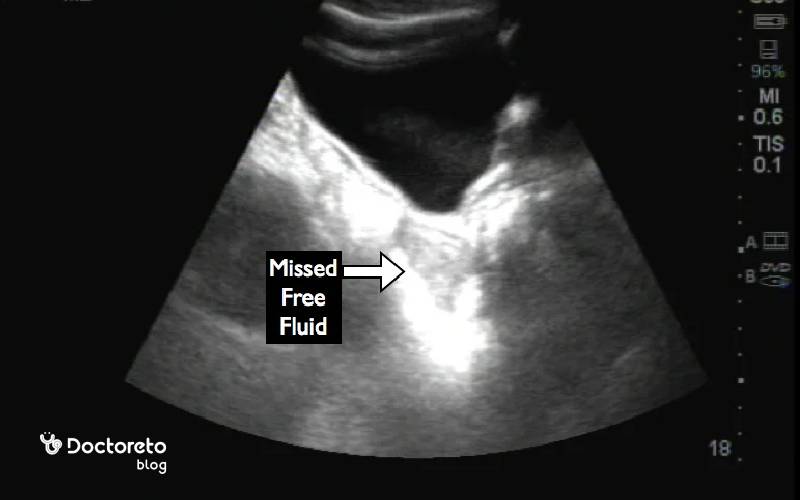

سونوگرافی مایع آزاد در لگن

بررسی مایع آزاد در لگن در سونوگرافی یکی از رایجترین و در دسترسترین روشها برای بررسی وجود و میزان مایع در ناحیه لگن است. این روش کاملاً غیرتهاجمی، بدون درد و ایمن بوده و معمولاً بهصورت سونوگرافی شکمی یا واژینال (در خانمها) انجام میشود. پزشک با استفاده از سونوگرافی میتواند محل تجمع مایع، حجم آن و ارتباط آن با اندامهای اطراف را بررسی کند.

مقدار کم مایع آزاد در لگن، بهویژه در زمان تخمکگذاری، اغلب طبیعی تلقی میشود و نیاز به اقدام خاصی ندارد. اما اگر حجم مایع زیاد باشد یا همراه با نشانههایی مثل درد، تب یا یافتههای غیرطبیعی دیگر دیده شود، ممکن است نشانه عفونت لگنی، خونریزی داخلی، پارگی کیست تخمدان یا بارداری خارجرحمی باشد. تفسیر نتایج سونوگرافی همیشه باید در کنار علائم بالینی، سن بیمار و زمان چرخه قاعدگی انجام شود. در برخی موارد، پزشک ممکن است برای تشخیص دقیقتر، آزمایشهای تکمیلی، سونوگرافی پیگیری یا روشهای تصویربرداری دیگر را توصیه کند.